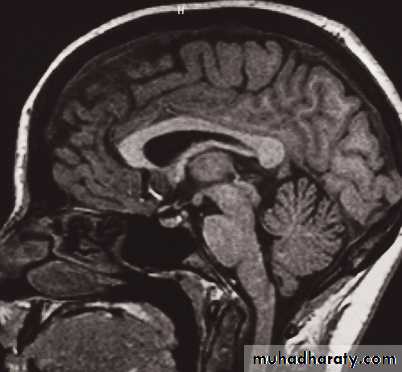

MRI of the brain

• Axial, coronal and sagittal projections are all considered standard• T1-weighted and T2-weighted images.

• It is possible to recognize flowing blood and, therefore, the larger arteries and veins stand out clearly without the need for contrast medium.

• The characteristics of grey and white matter are different, and both are clearly different from the CSF in the ventricular system and subarachnoid space.

• The disadvantages of MRI compared with CT are the inability to show calcification, lack of bone detail, the relative expense of the technique, and the difficulty of monitoring seriously ill patients

• IV contrast in T1 WI

• MRA and MRV, Recent advances of MRI: perfusion, diffusion, spectroscopy, functional MRI, and tractography